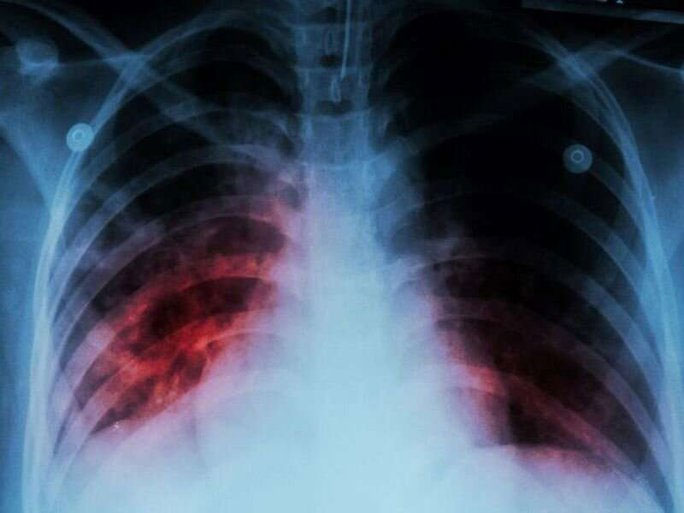

Một ca mắc bệnh lao ở Mỹ - (Ảnh: CDC).